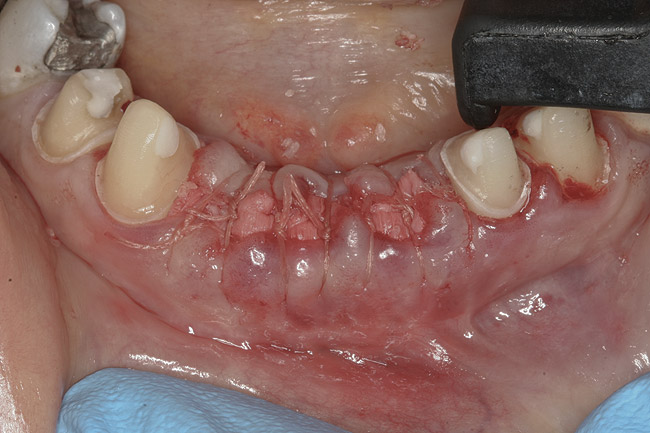

The final treatment plan called for replacement of teeth Nos. 24 through 26 with implants, and four adjacent porcelain crowns. The restorative dentist prepared these four teeth for full coverage and decoronated Nos. 24 and 25, then, with patient input, selected a shade (Figure 3) and fabricated a bis-acryl temporary bridge from Nos. 22 to 28. After extracting teeth Nos. 24 and 25, the periodontist performed socket preservation in addition to horizontal ridge augmentation in site No. 26 with FDBA and a resorbable porcine collagen membrane. The flaps were approximated with 4-0 polyglactin 910 (Figure 4). Figure 5 shows the 7-unit bis-acryl temporary bridge.

Figure 4  Extraction sites Nos. 24 and 25 after socket augmentation; additional grafting, site No. 26; flaps approximated with 4-0 polyglactin 910 sutures.

Figure 4